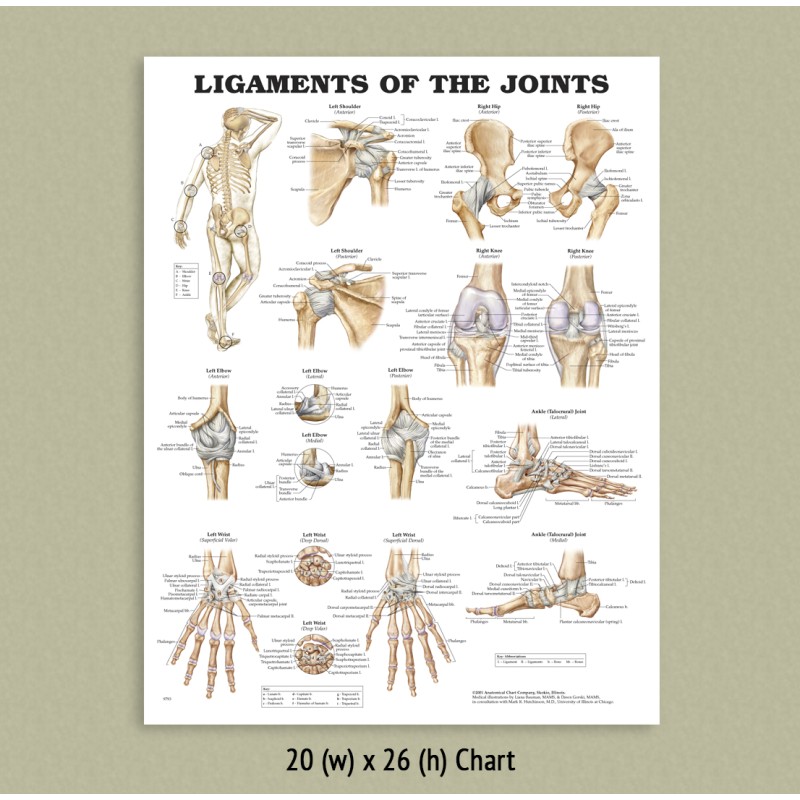

- Back Talk Systems, Colorado » Ligaments Of The Joints Anatomical Chart